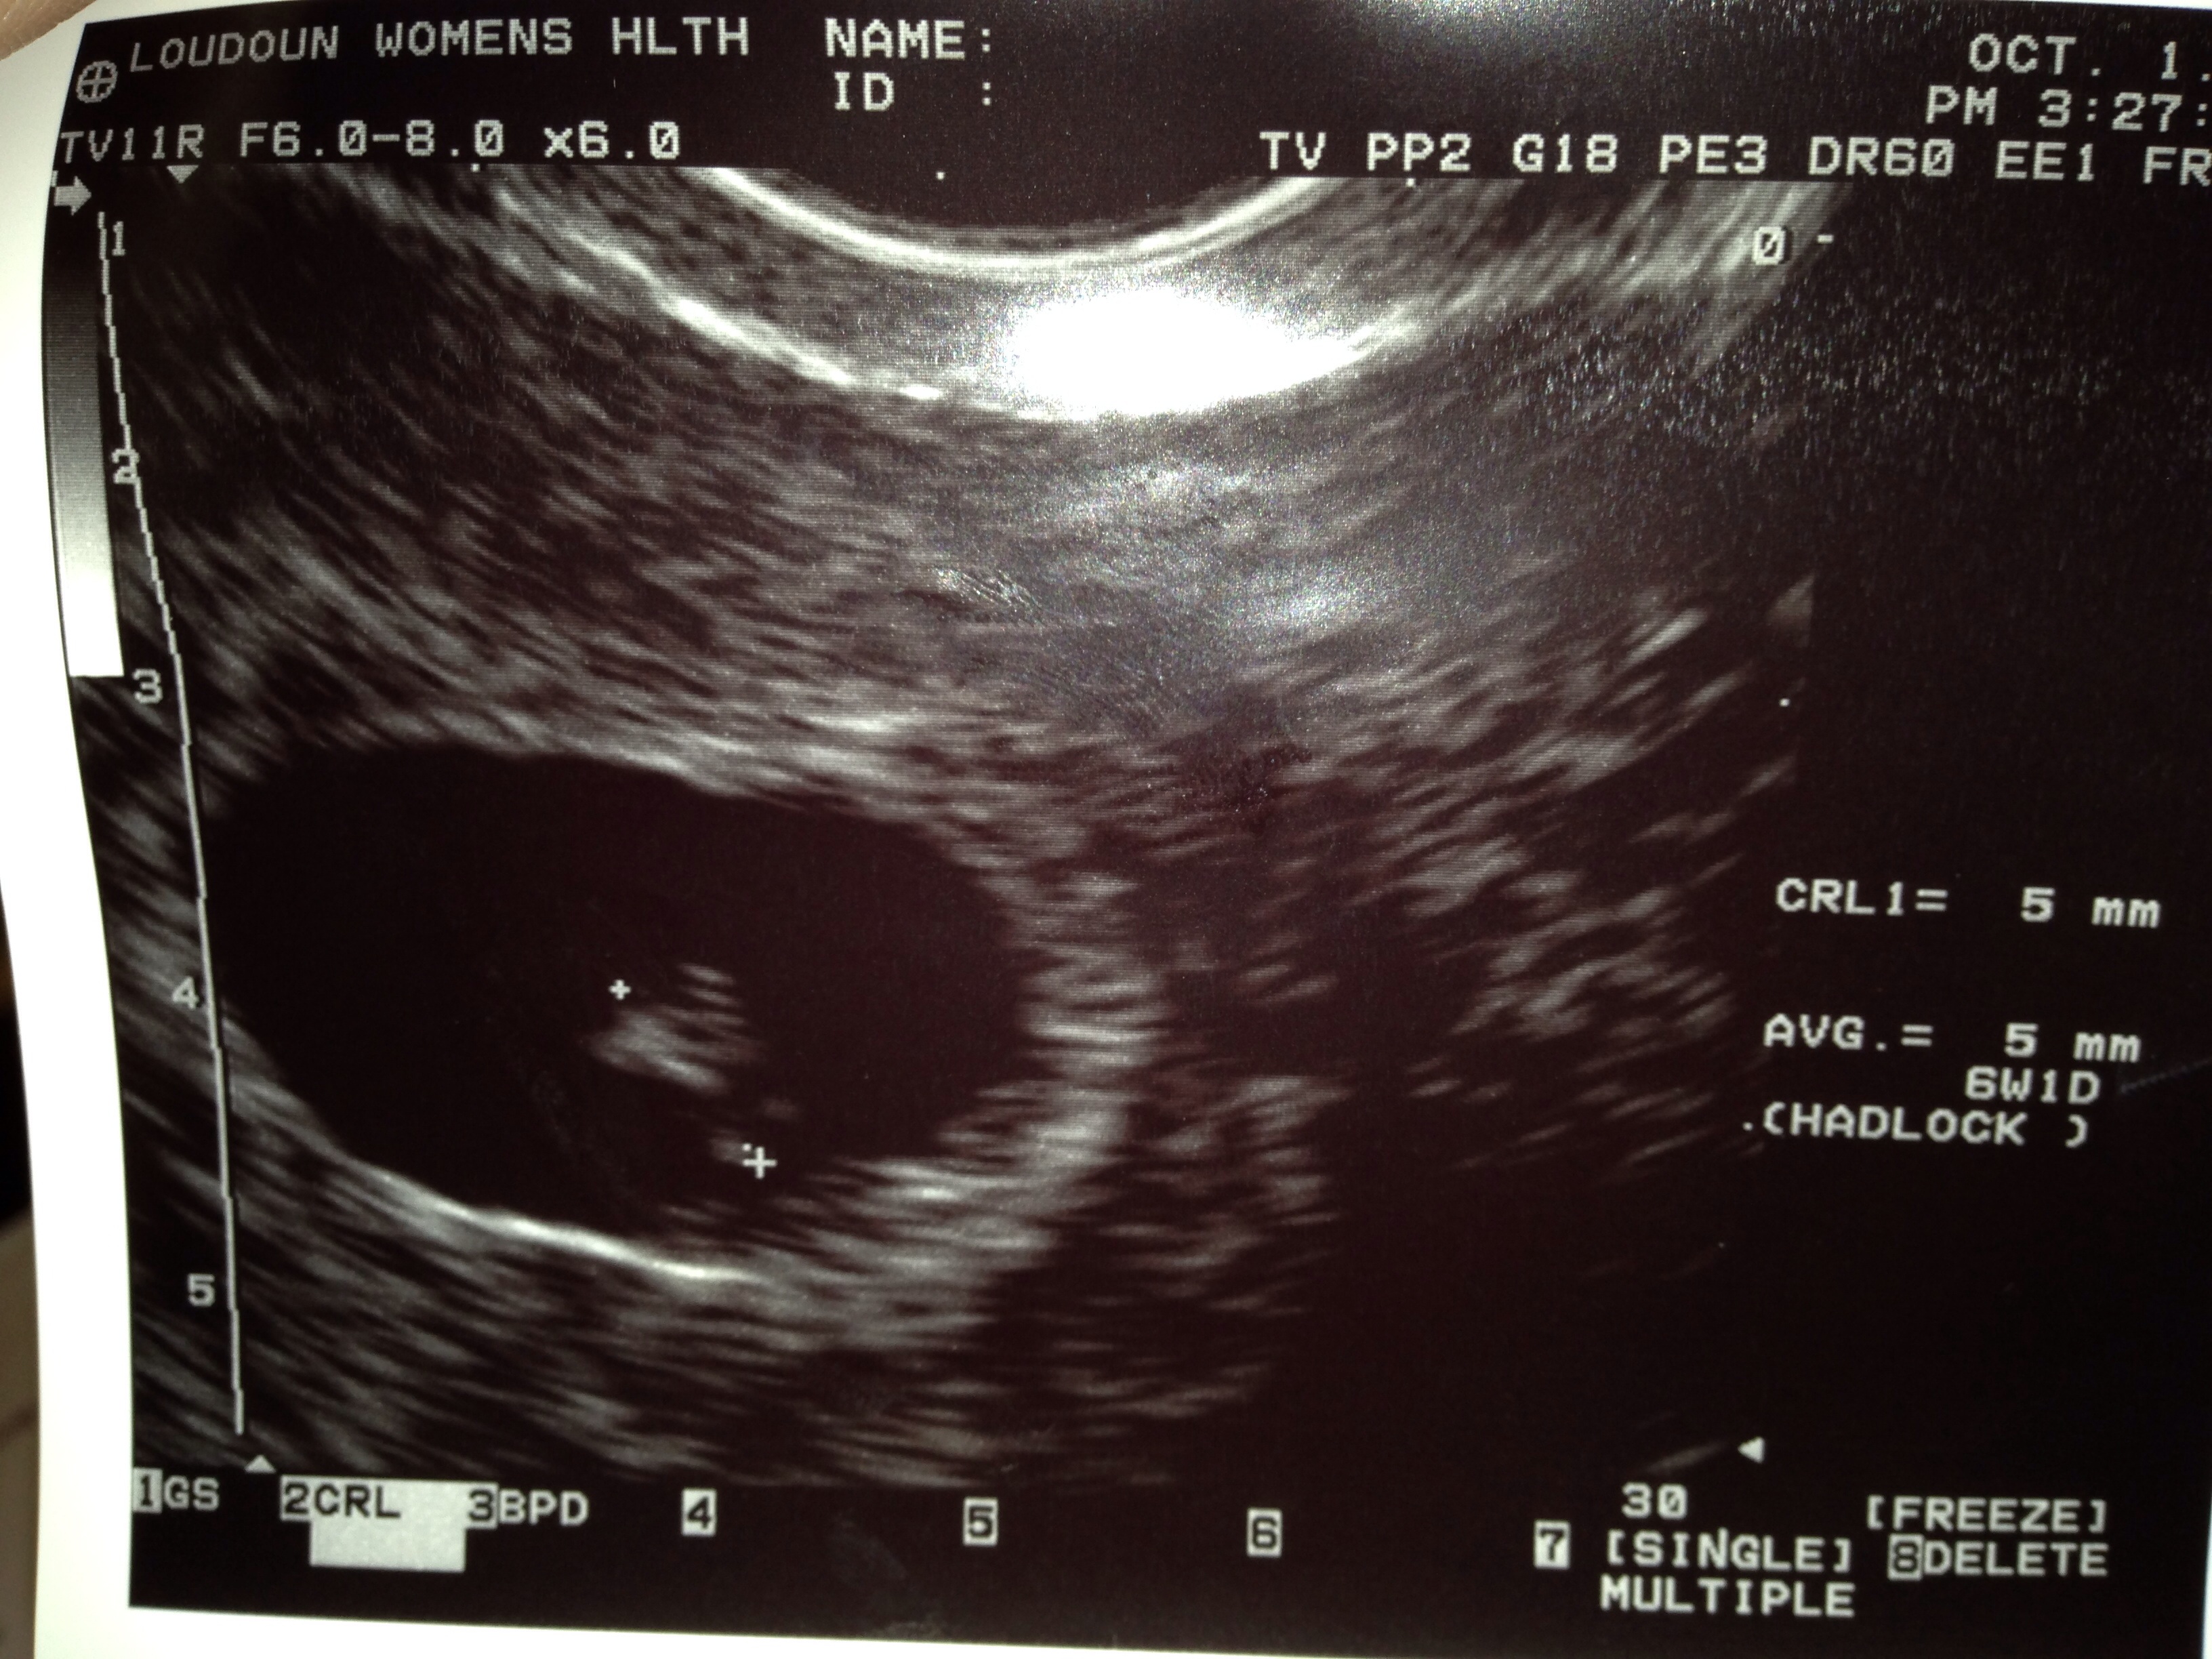

I know the Ramzi theory has all kinds of variables that make it unreliable, but I'd appreciate a guess for fun. This was transvaginal at 6 weeks 1 day. Also, I noticed with the same ultrasound for my daughter she was on the left side of the image. Do any women have experiences having early ultrasounds of the same gender on different sides? Thanks!

Attachment 21303